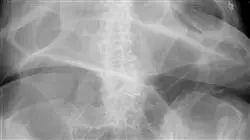

1.10. Tests complémentaires et radiologiques

Le syndrome obstructif défécatoire est une pathologie de plus en plus fréquente dans la population adulte. Il s'agit d'une affection du plancher pelvien qui peut provoquer un large éventail de symptômes, tels que la constipation chronique, des douleurs abdominales et des problèmes de défécation. Grâce à ce Certificat en Syndrome Défécatoire Obstructif, vous pourrez maîtriser les derniers postulats scientifiques en anatomie appliqués à cette pathologie, l'étiopathogénie, l'anamnèse et l'examen physique. De plus, vous aurez l'occasion d'apprendre des meilleurs experts en intervention clinique et en recherche dans ce domaine de travail passionnant.